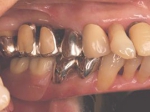

片側2歯欠損 主訴-入れ歯を使ってみたが違和感強くてダメ。固定のものにしたい。術前下顎口腔内(鏡像)